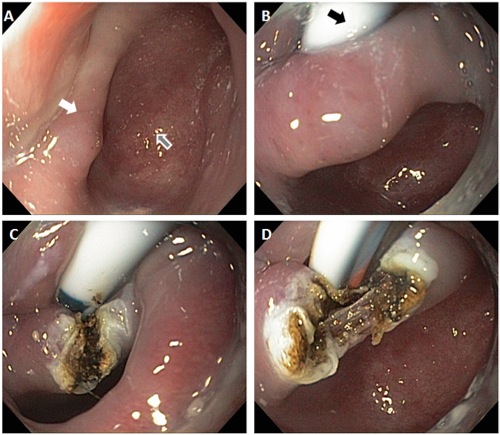

Zenker’s diverticulum (also known as an oesophageal pouch, grey arrow Figure A below) may cause difficulty with swallowing, choking attacks, regurgitation and halitosis (bad breath). Most of these symptoms are due to retention of food debris or liquids within the pouch.

Your doctor will first discuss the risks of the procedure with you and address any questions you may have. You will then meet your anaesthetist who will discuss all aspects of the anaesthetic. Following this you will be taken to the procedure room. You'll then lie on your side, and a needle will be placed in your hand or arm. This is used to administer the anaesthetic. Once you are completely asleep your doctor will pass the endoscope through your mouth and into the oesophagus, stomach and duodenum. A flexible feeding tube will be placed through the mouth and into the stomach (B, black arrow). This is attached to the side of your face using adhesive tape. The muscle ridge that separates the diverticulum from the oesophagus is then incised using endoscopic instruments (C and D) and the incision is closed using an endoscopic clip. The procedure usually takes around 30-45 minutes and you will then be taken to the recovery area.